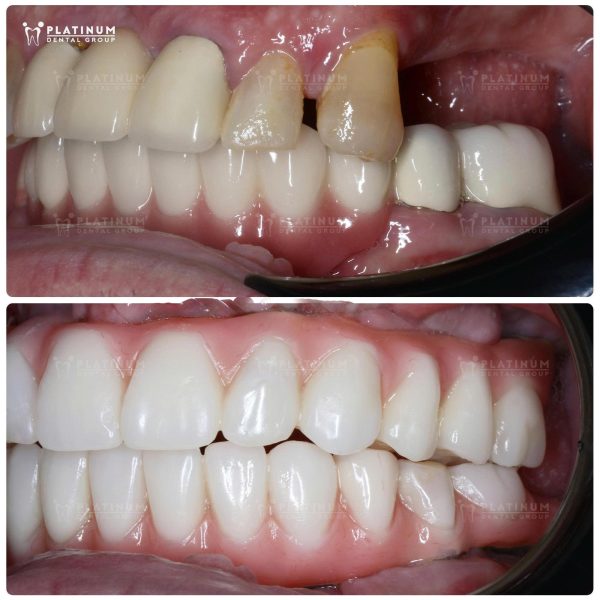

Mr. Mario và hành trình lột xác nụ cười nhờ cấy ghép Implant All-on-6

Trước khi tìm đến Platinum Dental Group, Mr. Mario phải sống chung với tình trạng mất toàn bộ răng, điều này không chỉ ảnh hưởng đến khả năng ăn nhai mà còn khiến anh gặp nhiều trở ngại trong sinh hoạt và giao tiếp. Những bữa ăn trở nên thiếu trọn vẹn và nụ cười dần biến mất vì sự tự ti kéo dài.

Giải pháp được lựa chọn cho anh là phương pháp cấy ghép Implant All-on-6 – phục hồi toàn diện cả về chức năng lẫn thẩm mỹ. Sau điều trị, Mr. Mario đã sở hữu một hàm răng chắc khỏe, đều đặn với màu sắc trắng sáng tự nhiên, form răng chuẩn tỉ lệ gương mặt và đường nét hài hòa. Kết quả không chỉ vượt mong đợi mà còn giúp anh tự tin hơn mỗi ngày với nụ cười trọn vẹn.